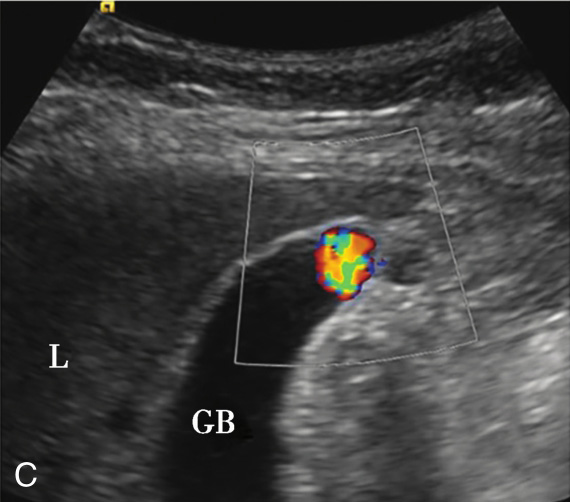

(1)局限型胆囊腺肌症:

好发于胆囊底部,灰阶超声图像通常呈边界清楚的低回声(图2-4-1A)。病变内部回声不均匀,能够观察到小片状无回声区,部分病变内可见点状高回声后伴彗星尾征(图2-4-1B)。CDFI通常无明显血流信号,部分病变内的点状高回声后方可见“快闪伪像”(图2-4-1C)。

图2-4-1 局限型胆囊腺肌症常规超声图像

A.胆囊底部低回声结节(箭头所示),边界清楚,形态规则;B.结节内可见点状高回声后伴彗星尾征(箭头所示);C.CDFI示结节内可见“快闪伪像”

GB:胆囊